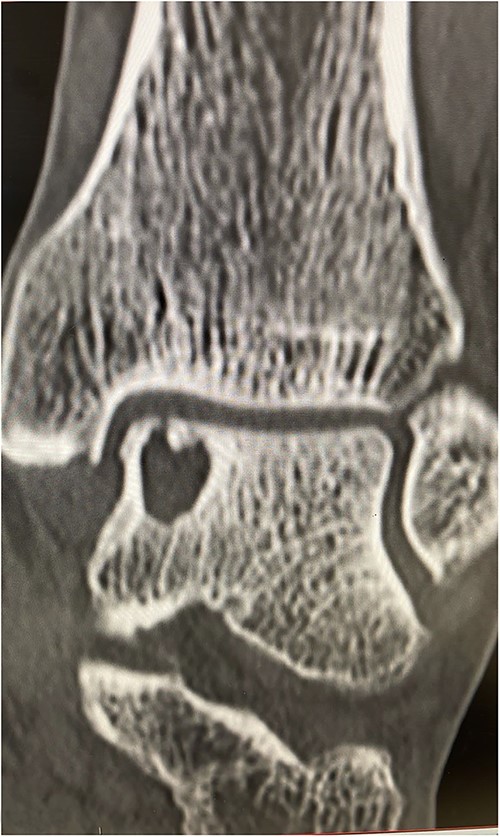

An X-ray of the ankle showed a radiolucency at the anteromedial aspect of the talus, suggesting a subchondral cyst. This lesion measured 18 × 18 × 11 mm on the CT scan in the medial patellar dome with a focal vacuum at the medial talocrural joint. The overlying cortex was thinned out with medial focal cortical defect. There was no collapse of the articular surface (Fig. 1).